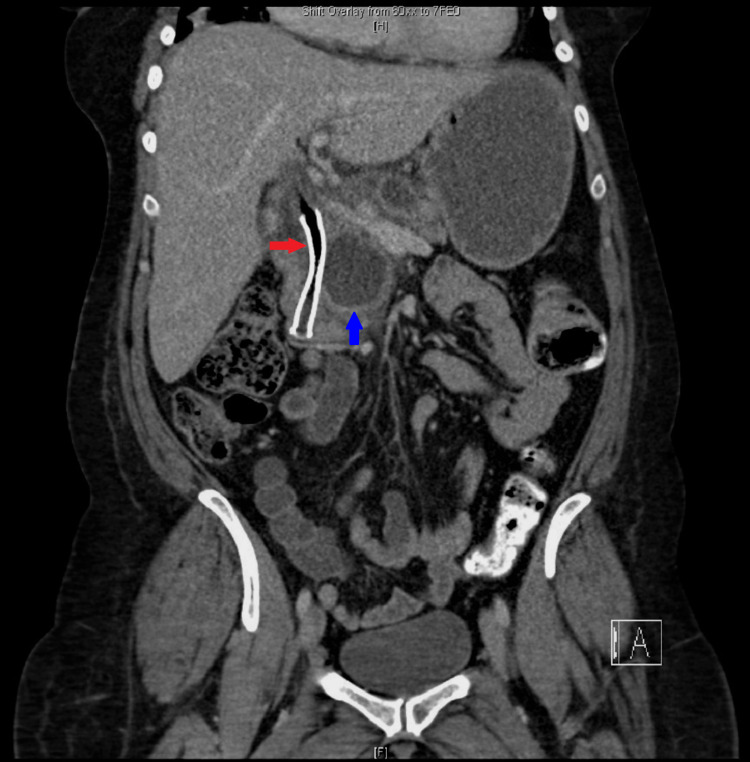

CT abdomen suggested recurrence of the pseudocyst in the pancreatic head, causing compression of the CBD and PD leading to dilatation of upstream PD, CBD, and intrahepatic biliary ducts. There was a further large cyst measuring 6.6 x 3.7 cm posterosuperior to the pancreas along with a larger right renal cyst. MRI confirmed evidence of chronic pancreatitis and two pancreatic pseudocysts. One of the cysts in the head of the pancreas measuring 4.8 x 4.6 cm was causing local pressure effect on the CBD, and there was intra and extrahepatic biliary dilatation with the CBD measuring up to 15 mm (previously 13 mm) (Figure 3). The cyst was also causing compression of the pancreatic duct, which was dilated to approximately 7 mm. The other large peripancreatic cyst measuring about 7 x 4 cm located posterosuperior to the body of pancreas had ruptured causing collection sized 12.9 x 11.2 x 13.0 cm, compressing on the right renal capsule (Figure 4).

Ultrasonography-guided percutaneous drainage of the cyst was performed. The fluid obtained from the drainage was turbid and bloody with no growth of microorganisms on culture and negative for malignant cells on cytology. Following the drainage, an endoscopic retrograde cholangiopancreatography (ERCP) was performed that showed a distal CBD stricture, which was stented using a fully covered self-expandable metal stent. Brushings retrieved during ERCP did not show any evidence of malignancy.